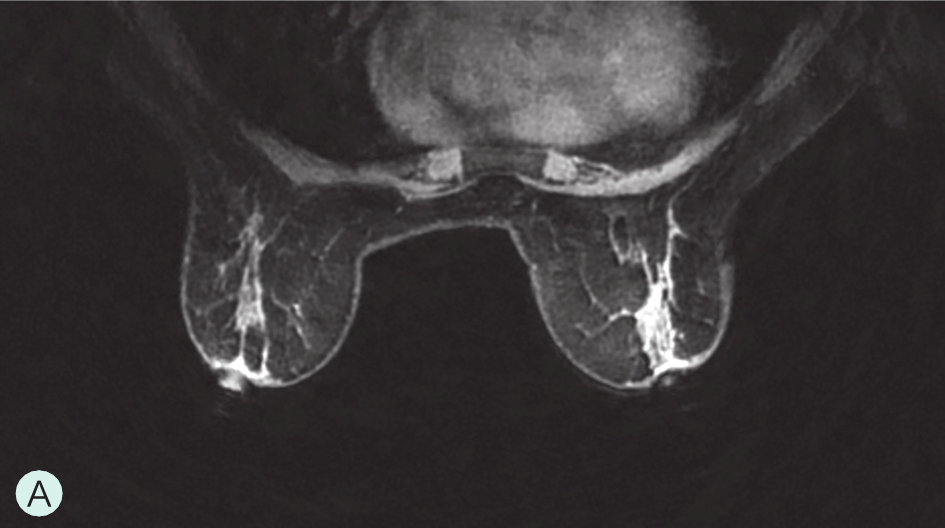

A级:几乎完全为脂肪型(图1-3-1A、图1-3-2A、图1-3-3A)。

图1-3-3 乳腺MRI不同乳腺密度

A.脂肪型;B.散在致密型;C.不均匀致密型;D.极度致密型